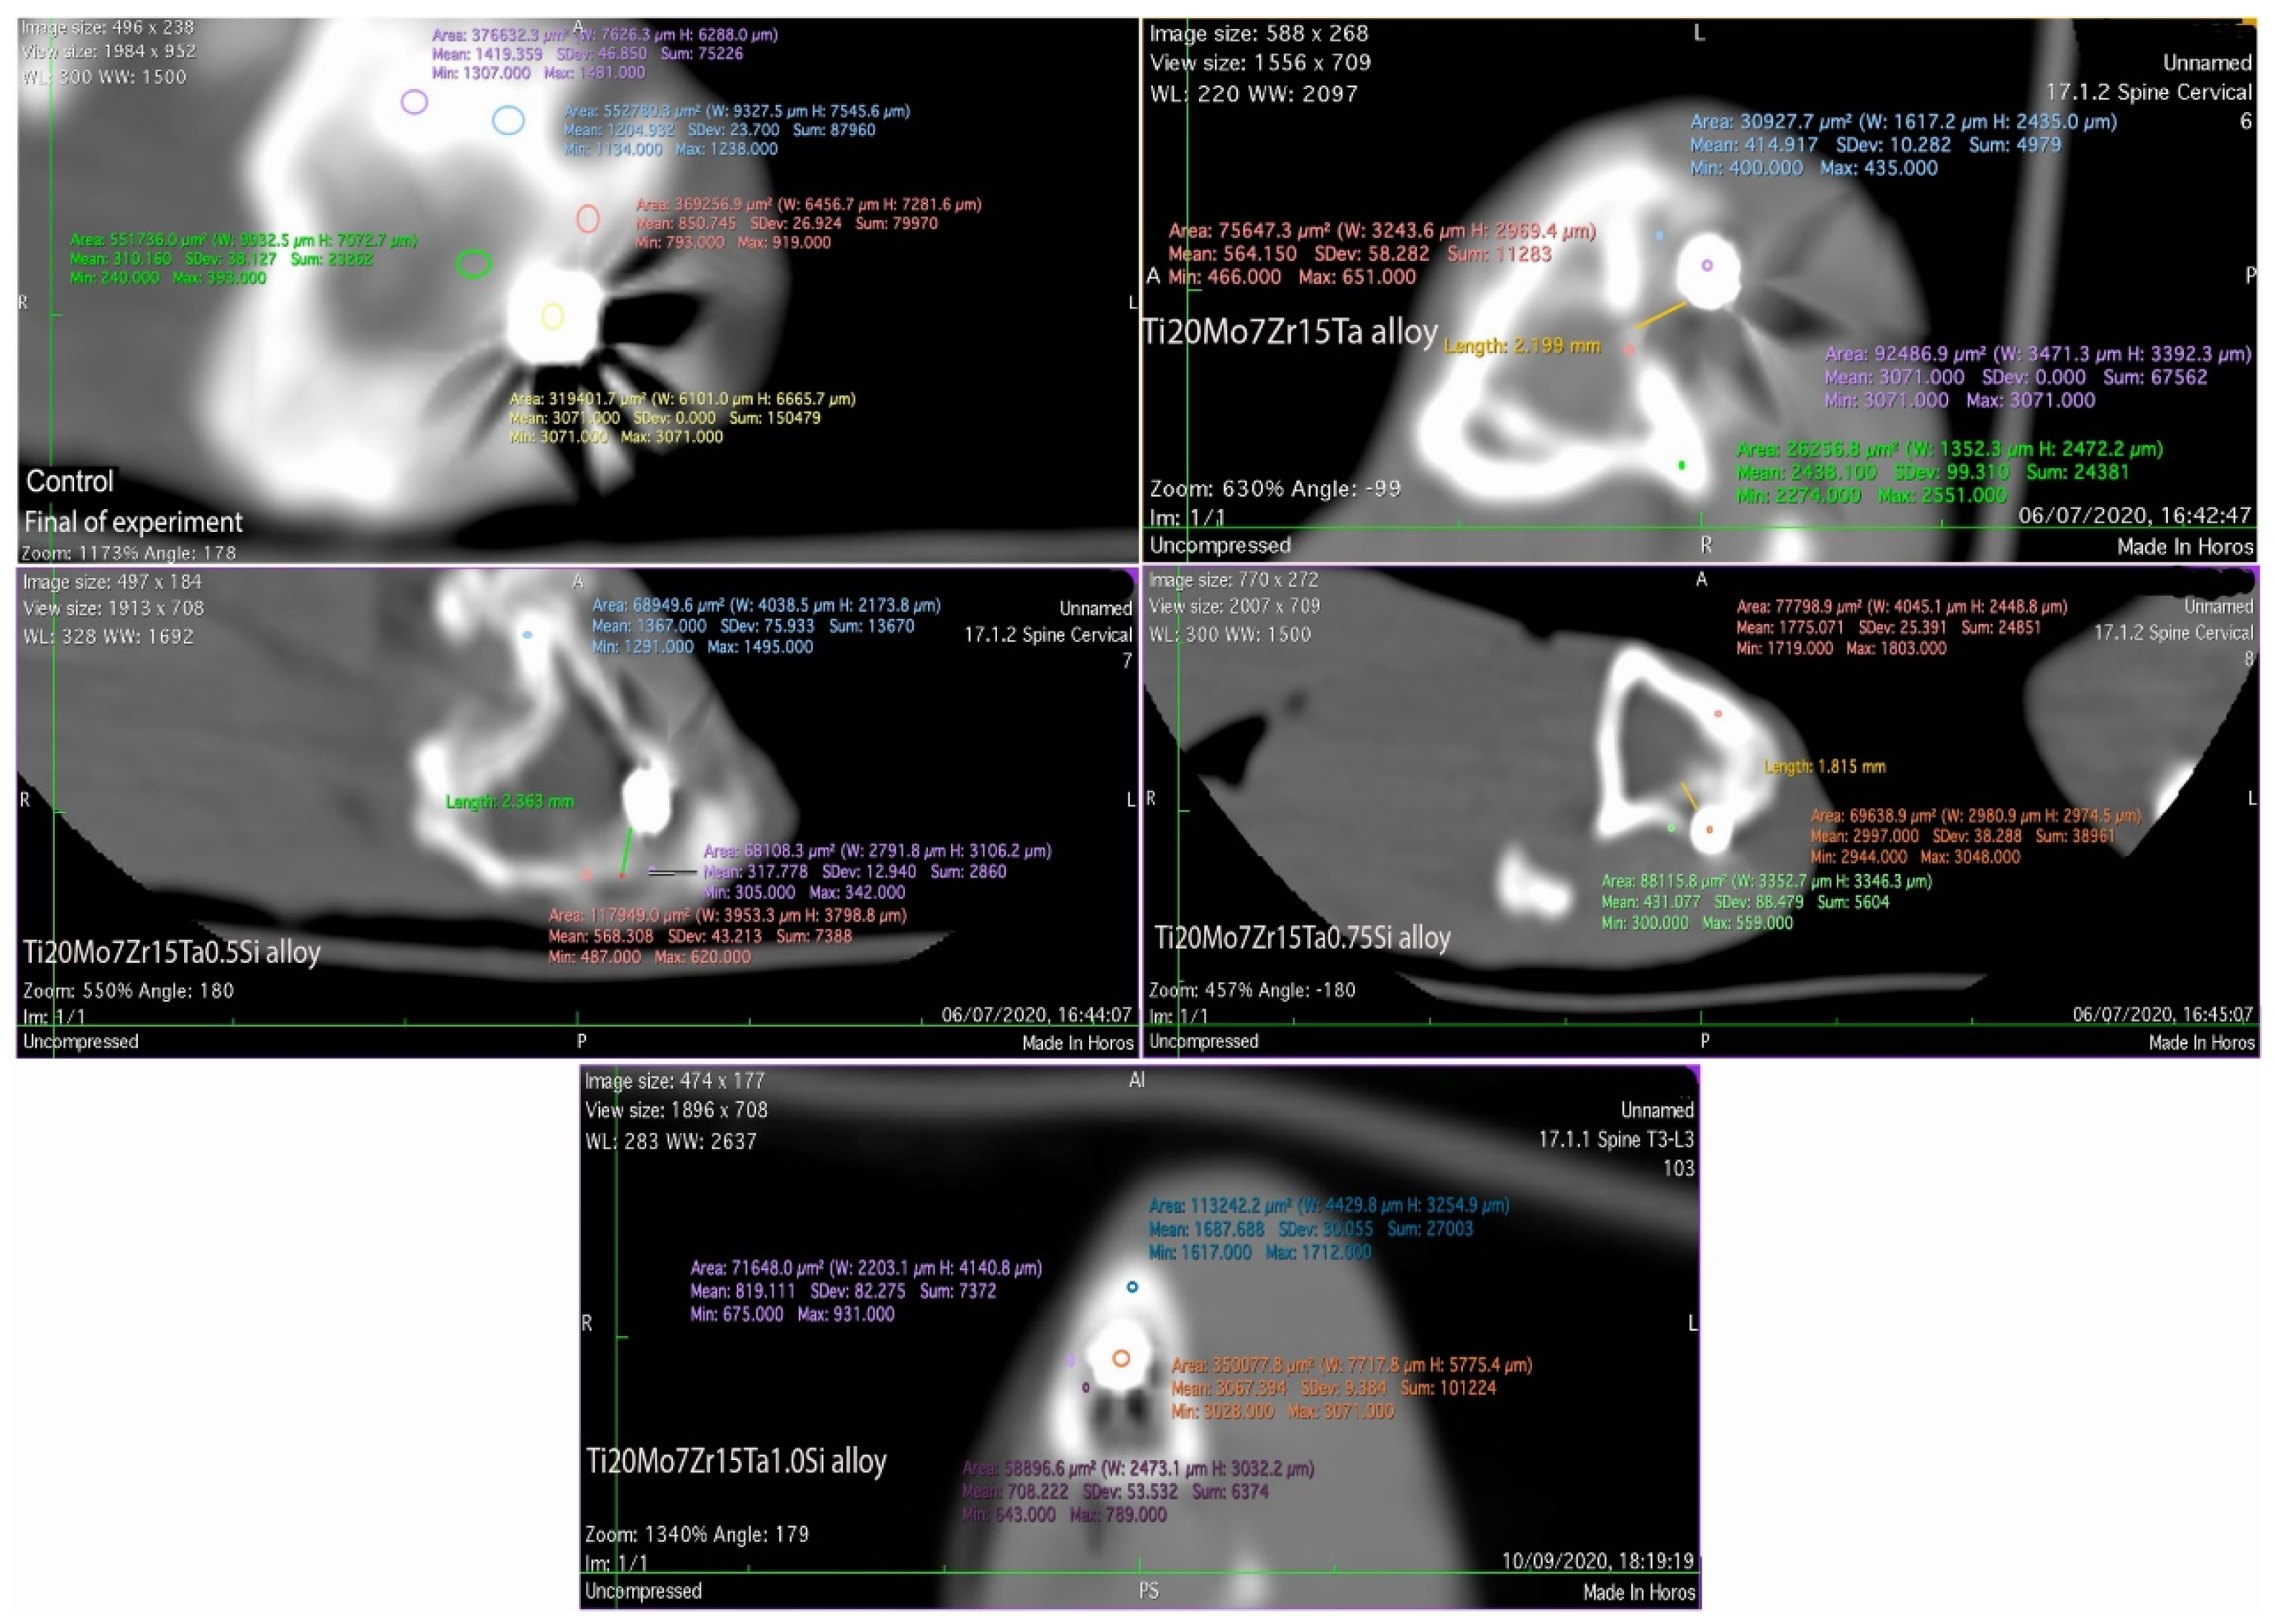

3.4. In Vivo Biocompatibility of Ti-Mo-Zr-Ta-Si Alloys